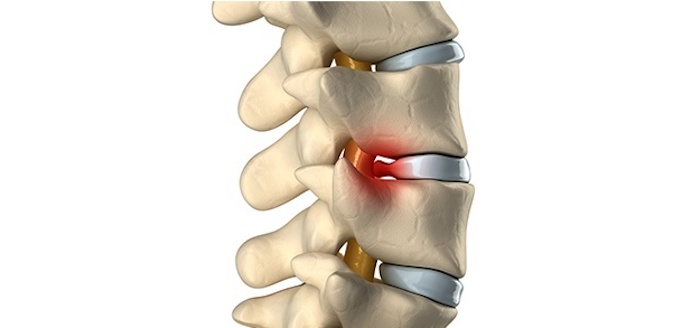

The management of pain is not only about treating the symptoms, but also about finding the underlying causes of pain and treating them through evidence-based and personalized treatment approaches. Whether you are experiencing muscle injuries and joint issues, nerve conditions and post-surgical pain, our experts assess your individual needs to offer specific, long-term pain relief.

- The use of nerve blocks, epidural injections, and radiofrequency ablation are minimally invasive interventions.

- Chronic back pain